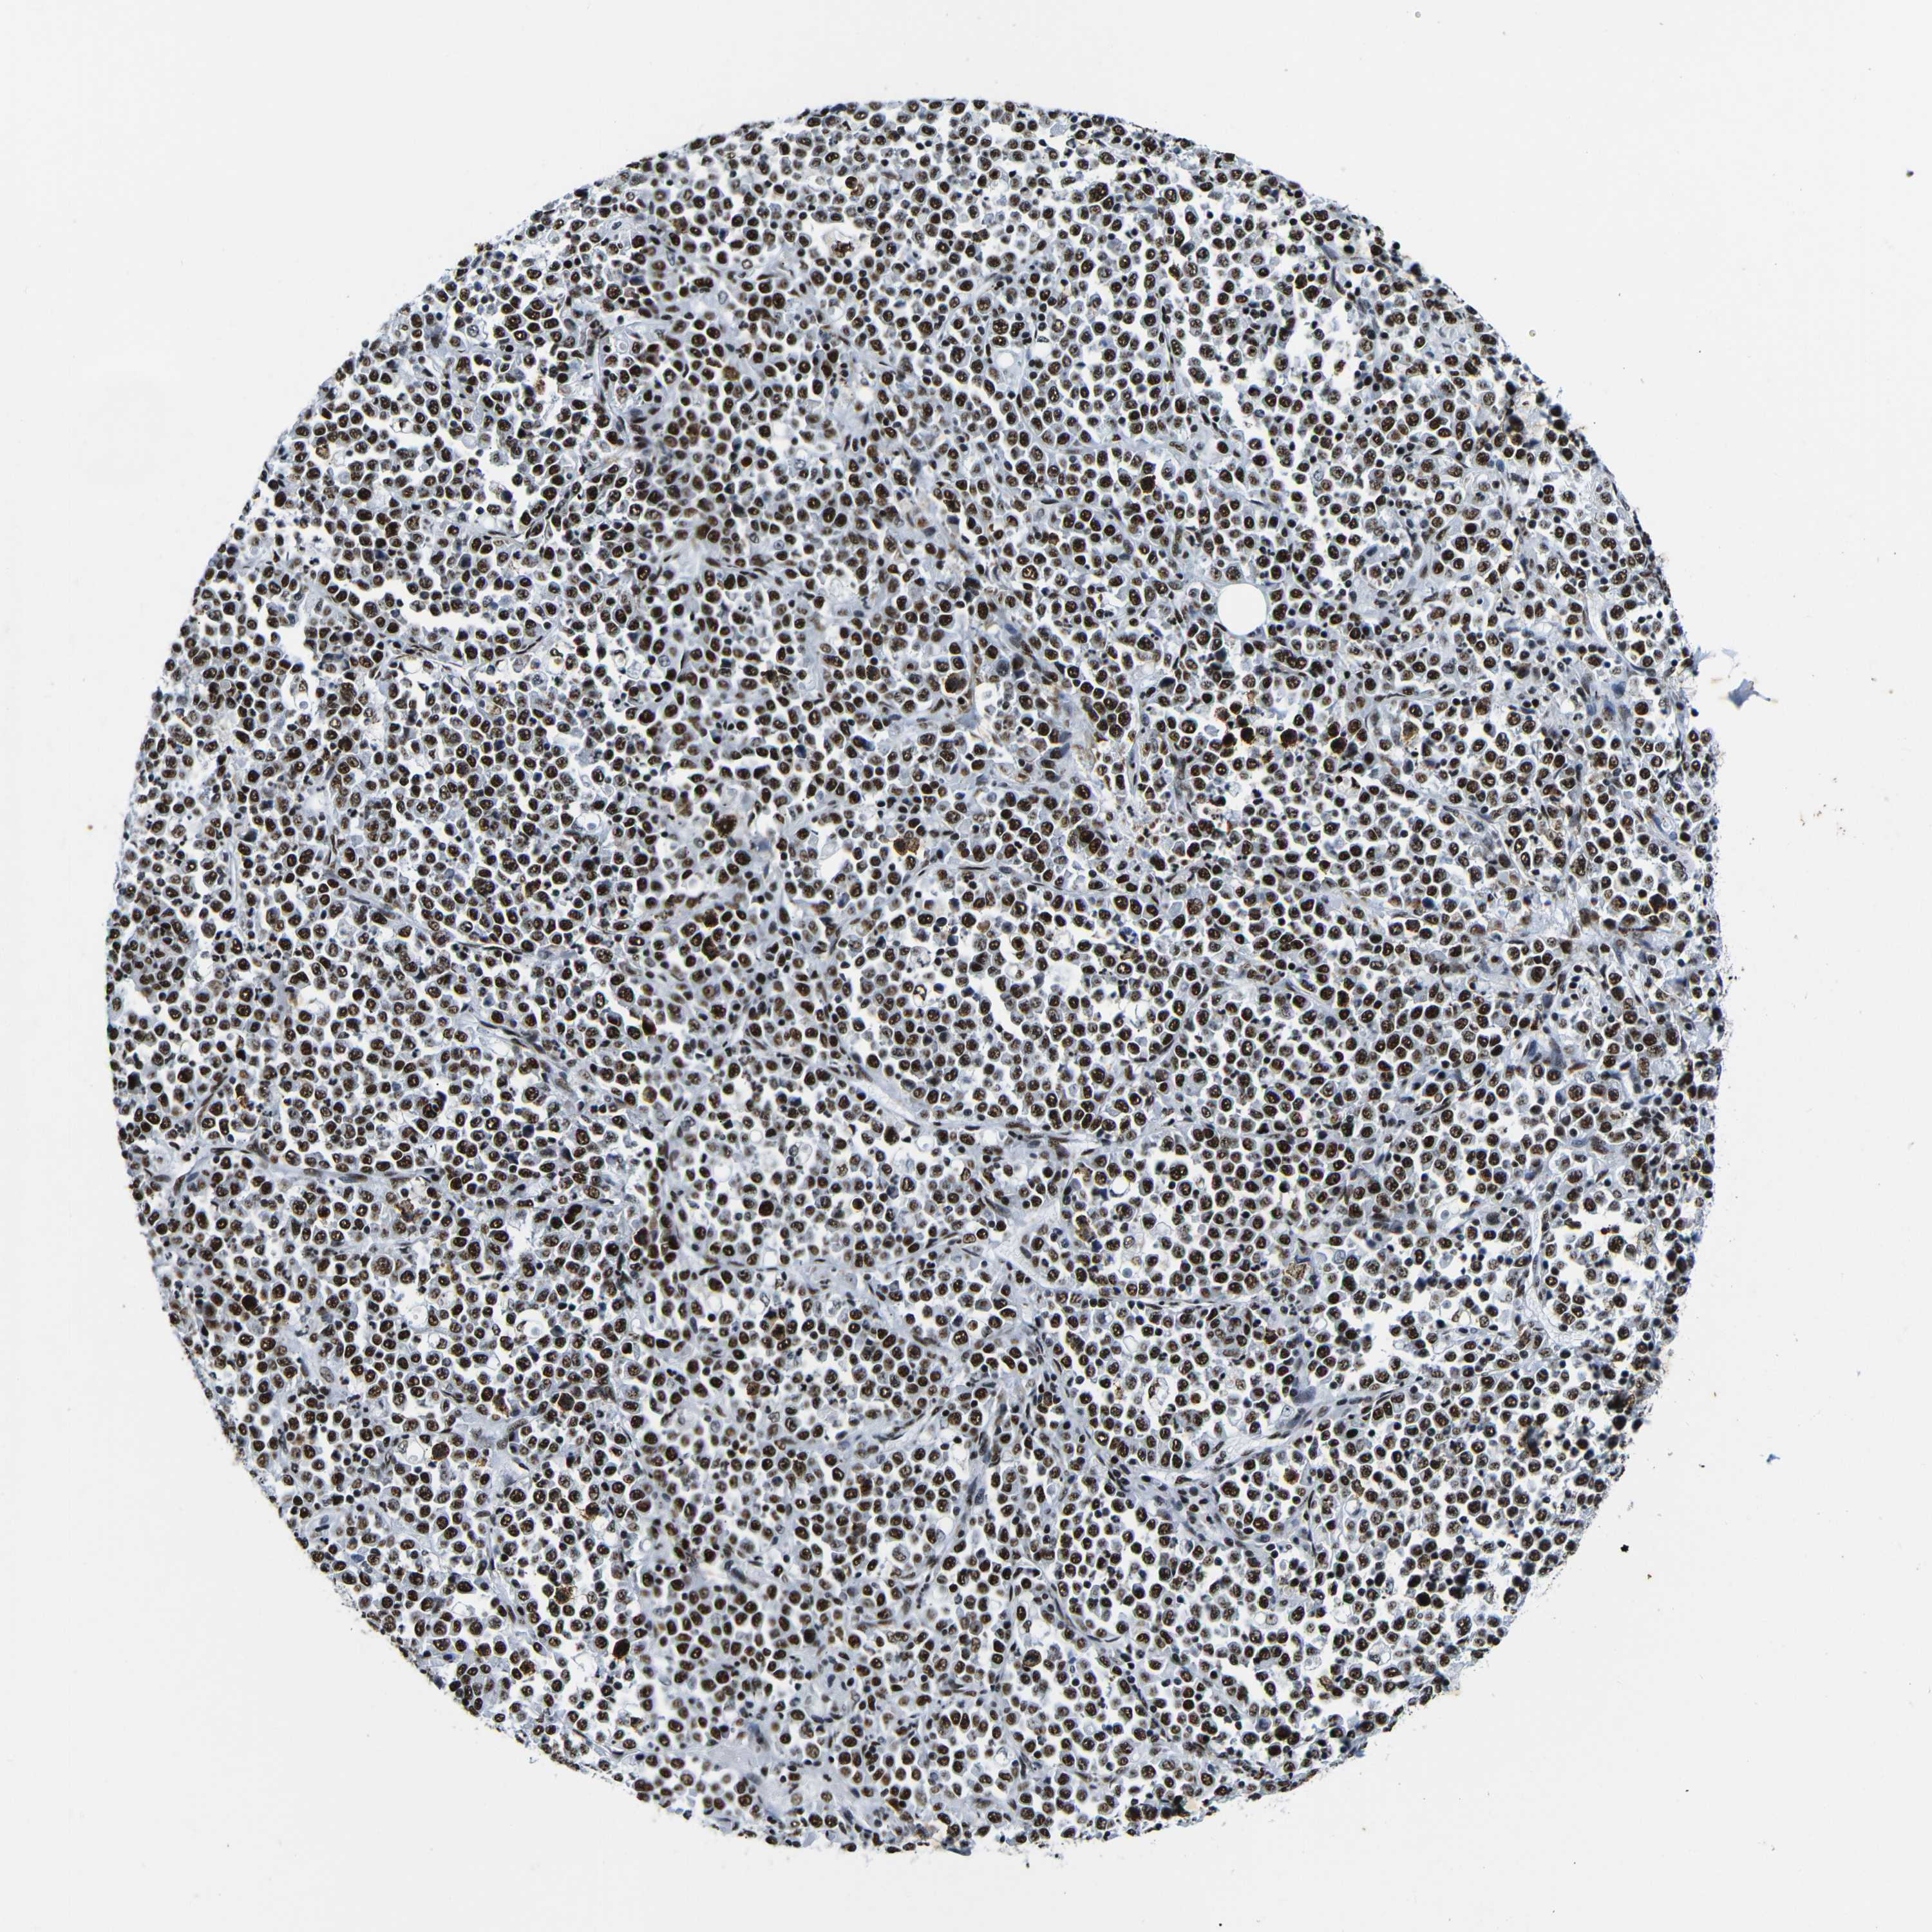

STOMACH CANCER - Protein expressioni

A mouse-over function shows sample information and annotation data. Click on an image to view it in a full screen mode. Samples can be filtered based on level of antibody staining by selecting one or several of the following categories: high, medium, low and not detected. The assay and annotation is described here.

Note that samples used for immunohistochemistry by the Human Protein Atlas do not correspond to samples in the TCGA dataset.

Antibody stainingi

Antibody staining in the annotated cell types in the current human tissue is reported as not detected, low, medium, or high, based on conventional immunohistochemistry profiling in selected tissues. This score is based on the combination of the staining intensity and fraction of stained cells.

Each image is clickable and will lead to virtual microscopy that enables deeper exploration of all samples and also displays staining intensity scores, fraction scores and subcellular localization as well as patient and tissue information for each sample.

Antibody HPA061301

Antibody CAB013073

Staining

High

Medium

Low

Not detected

Intensity

Strong

Moderate

Weak

Negative

Quantity

>75%

75%-25%

<25%

None

Location

Nuclear

Cytoplasmic/membranous

Cytoplasmic/membranous,nuclear

Adenocarcinoma, NOS

Adenocarcinoma, High grade